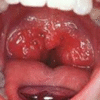

Häälekabinet Ida-Tallinna Keskhaiglas loodi 2008. aasta lõpus häälehäirete diagnostikaks. Diagnostika toimub fleksiibelse videolarüngostroboskoobiga, millega saab kõristruktuure täpsemini uurida, selgitamaks häälehäirete põhjusi. Videolarüngoskoopilisele (VLG) uuringule pöördutakse perearsti või eriarsti (sagedamini KNK-arsti, neuroloogi, pulmonoloogi, gastroenteroloogi) suunamisel. Põhikaebuseks on hääleprobleemid, mida pole ambulatoorsel vastuvõtul indirektse larüngoskoopiaga (joonis 1) diagnoosida õnnestunud. Viimast on keerulisem teostada elava kõrirefleksi või anatoomiliste